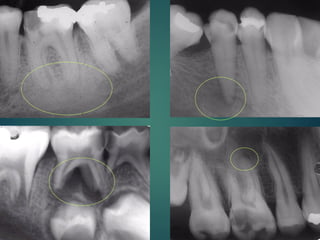

Clasificación

Radiográfica De las

Caries

 Incipiente de esmalte

 De esmalte

 Dentinaria superficial

 Dentinaria profunda

 Sobreproyectada en cámara pulpar

 Penetrante

Clasificación Radiográfica

De Las Caries